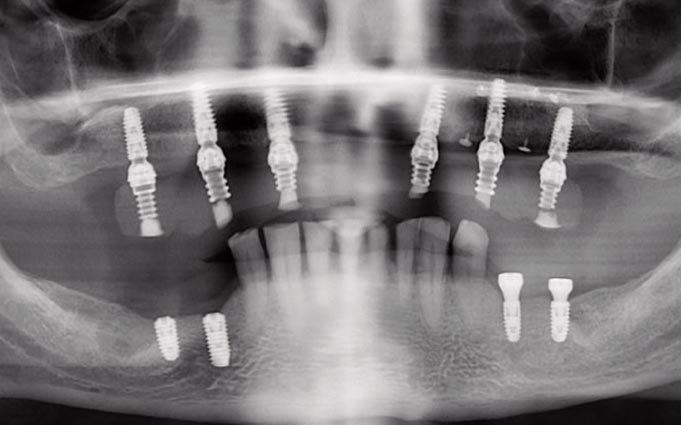

Медицинские Исследования: Кортикальная Пластинка на ОПТГ